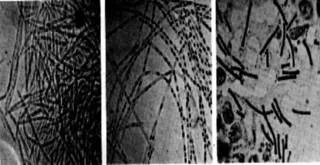

Antraks basilleri yoluyla çok bulaşıcı bir hayvan hastalığı olup insanlara doğrudan doğruya veya vasıtalı şekilde bulaşabilir. Genellikle keçilerde, koyunlarda, atlarda ve domuzlarda olur. Böylece, bu gibi hayvanlarla temasları olan insanların bu hastalığa tutulma oranları daha fazla olur.